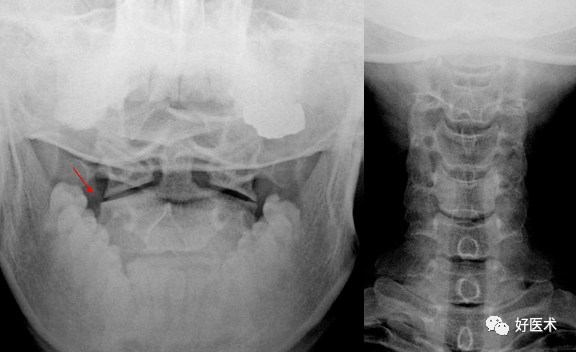

颈椎双边征

椎体旋转所致双边征双侧椎弓根形状不对称,钩椎关节间隙及椎弓关节

可出现以下征象双边征:即某1或2个椎体后缘呈双边状,颈椎旋转5°左右

3. 双边征

在正位片上出现棘突向一侧偏歪,标准侧位片上出现椎体双边征,双关节突

可出现以下征象双边征:即某1或2个椎体后缘呈双边状,颈椎旋转5